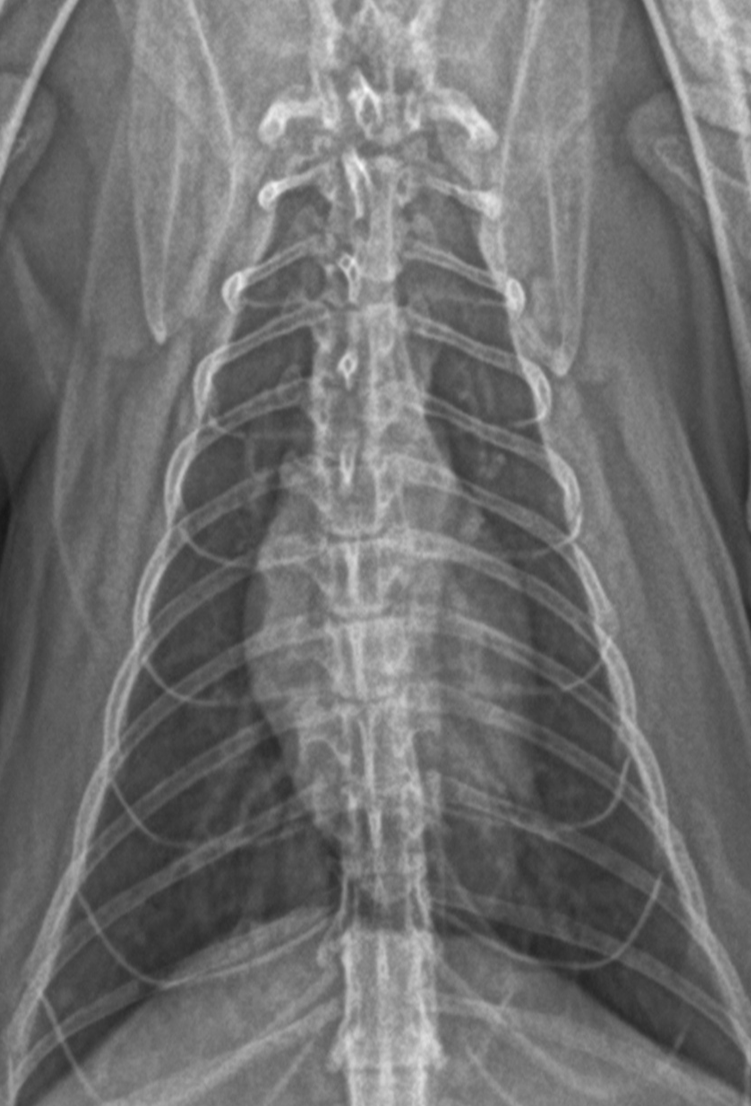

Оберіть рентгенівське зображення відповідно діагнозу.

View this question

Яка викладка (проекція) зображена на знімку:

рентген